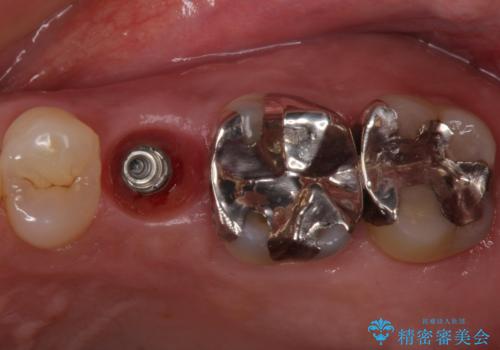

歯茎が腫れる インプラントでの治療

- 40代女性

- 10ヶ月

- 左上5/インプラント:242,000円 骨増生:55,000円 カスタムアバットメント:110,000円 インプラント用仮歯:22,000円 ジルコニアクラウン:121,000円 合計550,000円費用は治療当時の料金となります